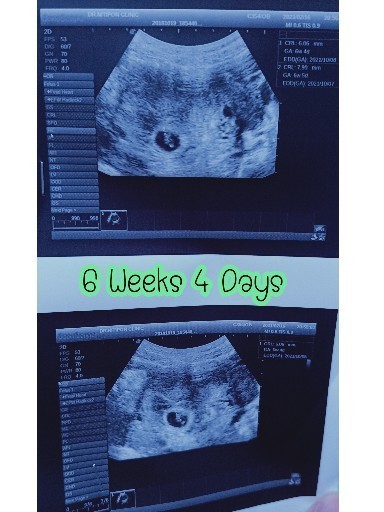

ซาวตอน6 สัปดาห์ หมอบอกยังไม่เจอน้อง อาจจะท้องลม แม่ๆบ้านไหนเป็นแบบนี้บ้างค่ะ

น่าจะอยู่ที่เครื่องด้วยค่ะเรา6+3